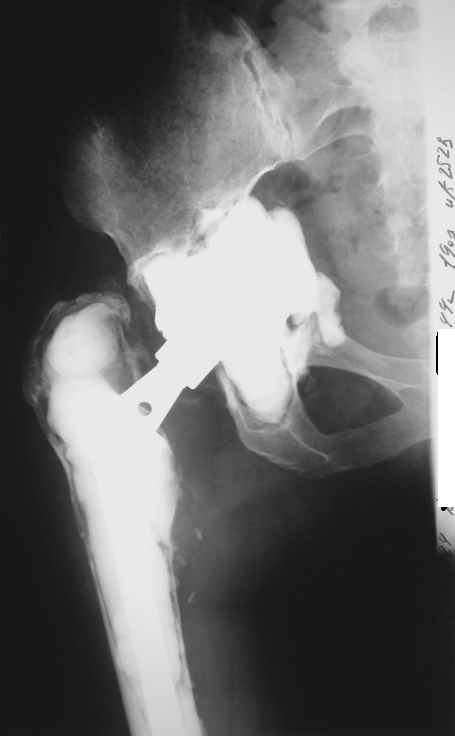

Апрель 2005 |  Декабрь 2005 |  Декабрь 2005 | Реревизия по поводу нестабильности вертлужногокомпонента была выполнена в апреле 2005 г. с пересадкой вертлужной впадины (аллотрансплантат)и защитой трансплантата кольцом Б-Ш.Нагноение выявлено через 6 месяцев, был полностью удален эндопротез (и вертлужный и бедренный компоненты), тщательная ХО мягких тканей с установкой подготовленной из цемента с антибиотиками (родной гентамицин + насыпной ванкомицин) вертлужной впадины опять же на цемент. Установлена новая ножка взамен удаленной на к/цемет с антибиотиками. Рана зажила, б-ая выписана домой. По этой методике прооперировано четверо б-х, пока без рецидива инфекции, одна из пациенток уже поступила для второго этапа.С уважением, Р.Тихилов

Большое спасибо за снимок, теперь все видно! Кстати, по этому поводу: в зоне бедренной кости кортикала осталось очень мало. Планируете ли Вы при окончательной имплантации менять эту ножку на другую (и если да, то на какую именно)?

Мы установили временный протез предназначенный только для движений и ходьбы без нагрузки. "Старый" цемент мы не удаляли поэтому спустя 3-4 месяца планируется выполнить расширенную остеотомию бедра с удалением всего к/цемента и установкой ножки бесцементной фиксации. Обязательным условием является хорошая дистальная фиксация на протяжении минимум 6-8 см. Скорее всего мы используем изогнутую ножку длиной 254 мм, это будет либо ZMR, либо Solution, я еще не планировал этот этап операции.